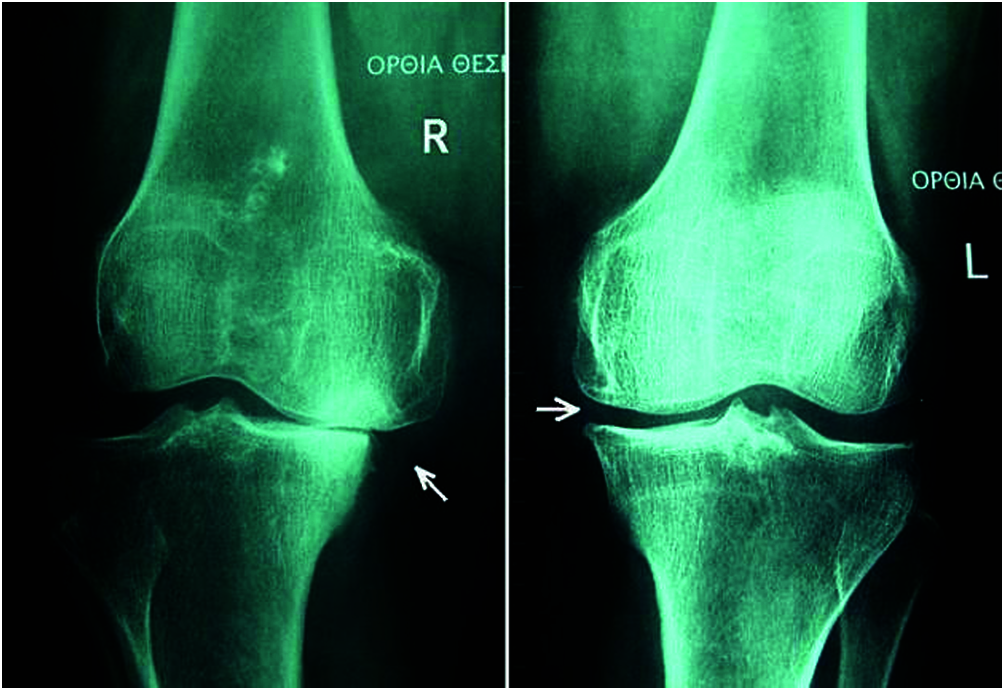

OA is a kind of joint disorder. Specialists claim that half of all people eventually build up some kind of suggestive OA in their lives. It can influence the hips, hands, and shoulders, and usually occurs in the knees. Fig. 3 shows a normal knee and one affected by OA. OA got progressively can be treated, where identifying it in the early stage is important for successful treatment [14]. The four phases of OA in each stage are discussed below.

Figure 3: Normal knee and affected knee OA

Preprocessing: The vector model of the DNN was used for the preprocessing mechanism. The vector model is an arithmetical model used for text reports as vectors of identifiers, such as terms in a list [22]. The vector model represents the dimensions of the given data and a simple slant for extracting the pertinent data from unclear datasets [23]. Fig. 6 shows X-ray images used for preprocessed preprocessing for knee OA (L & R).

Figure 6: X-ray of preprocessed Knee OA (L & R)